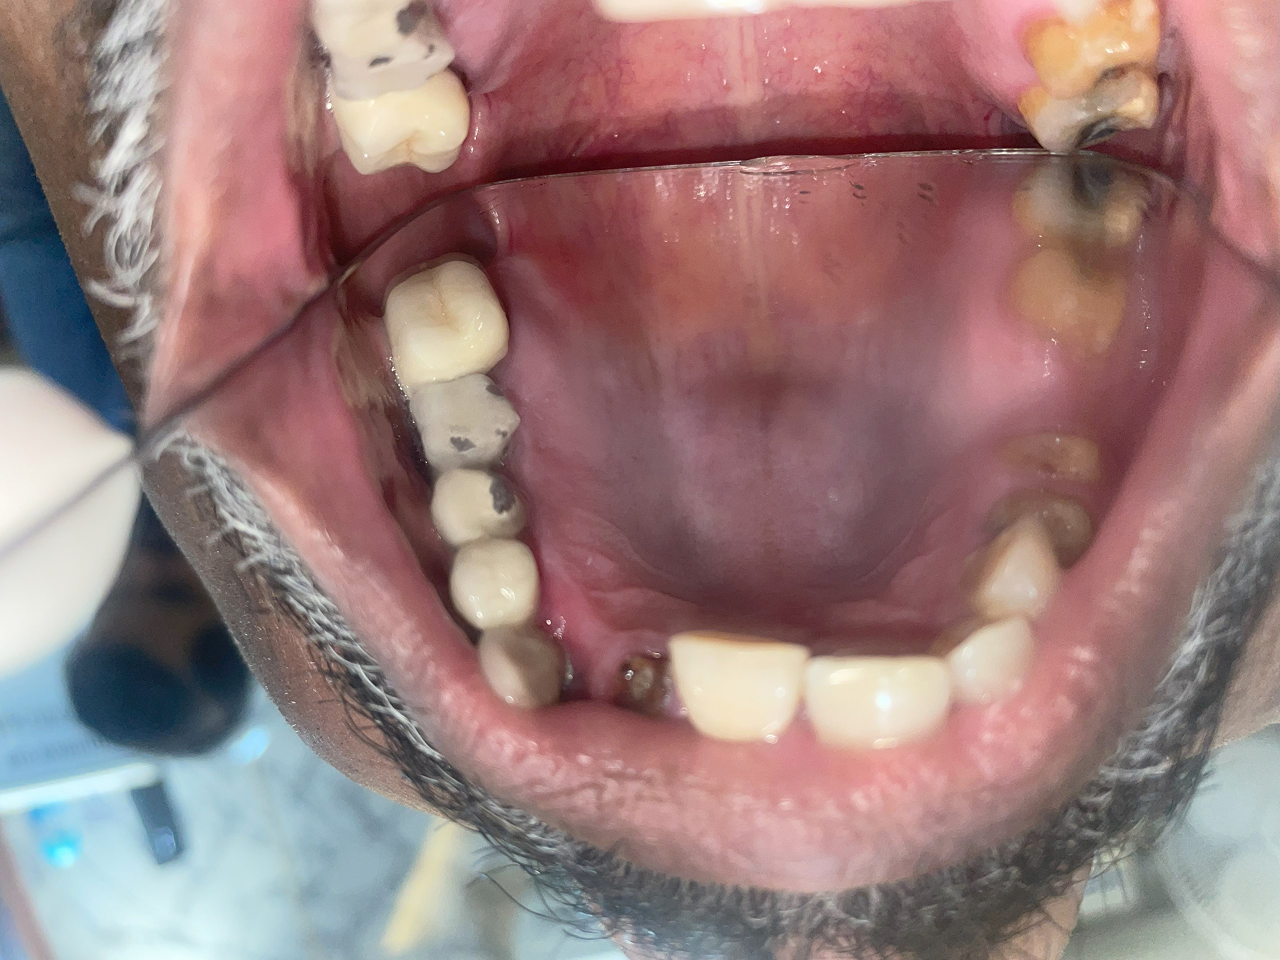

Full Mouth Rehabilitation

This includes comprehensive dental work such as implants, crowns, root canals, and other restorations to fully restore dental health and aesthetics.

Before treatment